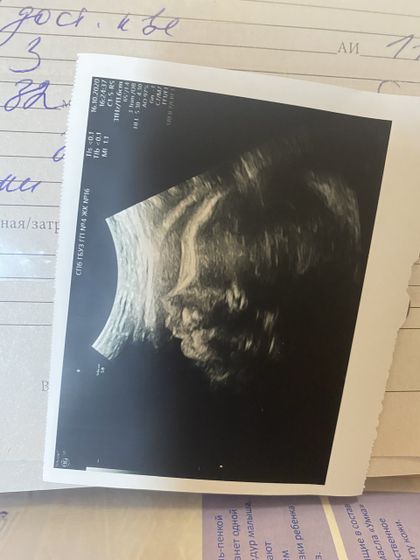

Мой сладкий ребёнок❤️Вчера был 3 скрининг, говорят все хорошо(моя душа наконец спокойна?) Как я была рада видеть свою маленькую врединку, которая не даёт делать спокойно узи, все бьет по аппарату и ругается на врача?Наш вес 1767 кг, уже большие совсем! Я так тебя люблю моя крошечка, скорей бы с тобой увидеться ?❣️Я так крепко люблю тебя??Дай бог всем такого счастья!

31,2 недельки?

1760 в 31.2

Какая красивая фоточка вышла?

Как будто улыбается ))